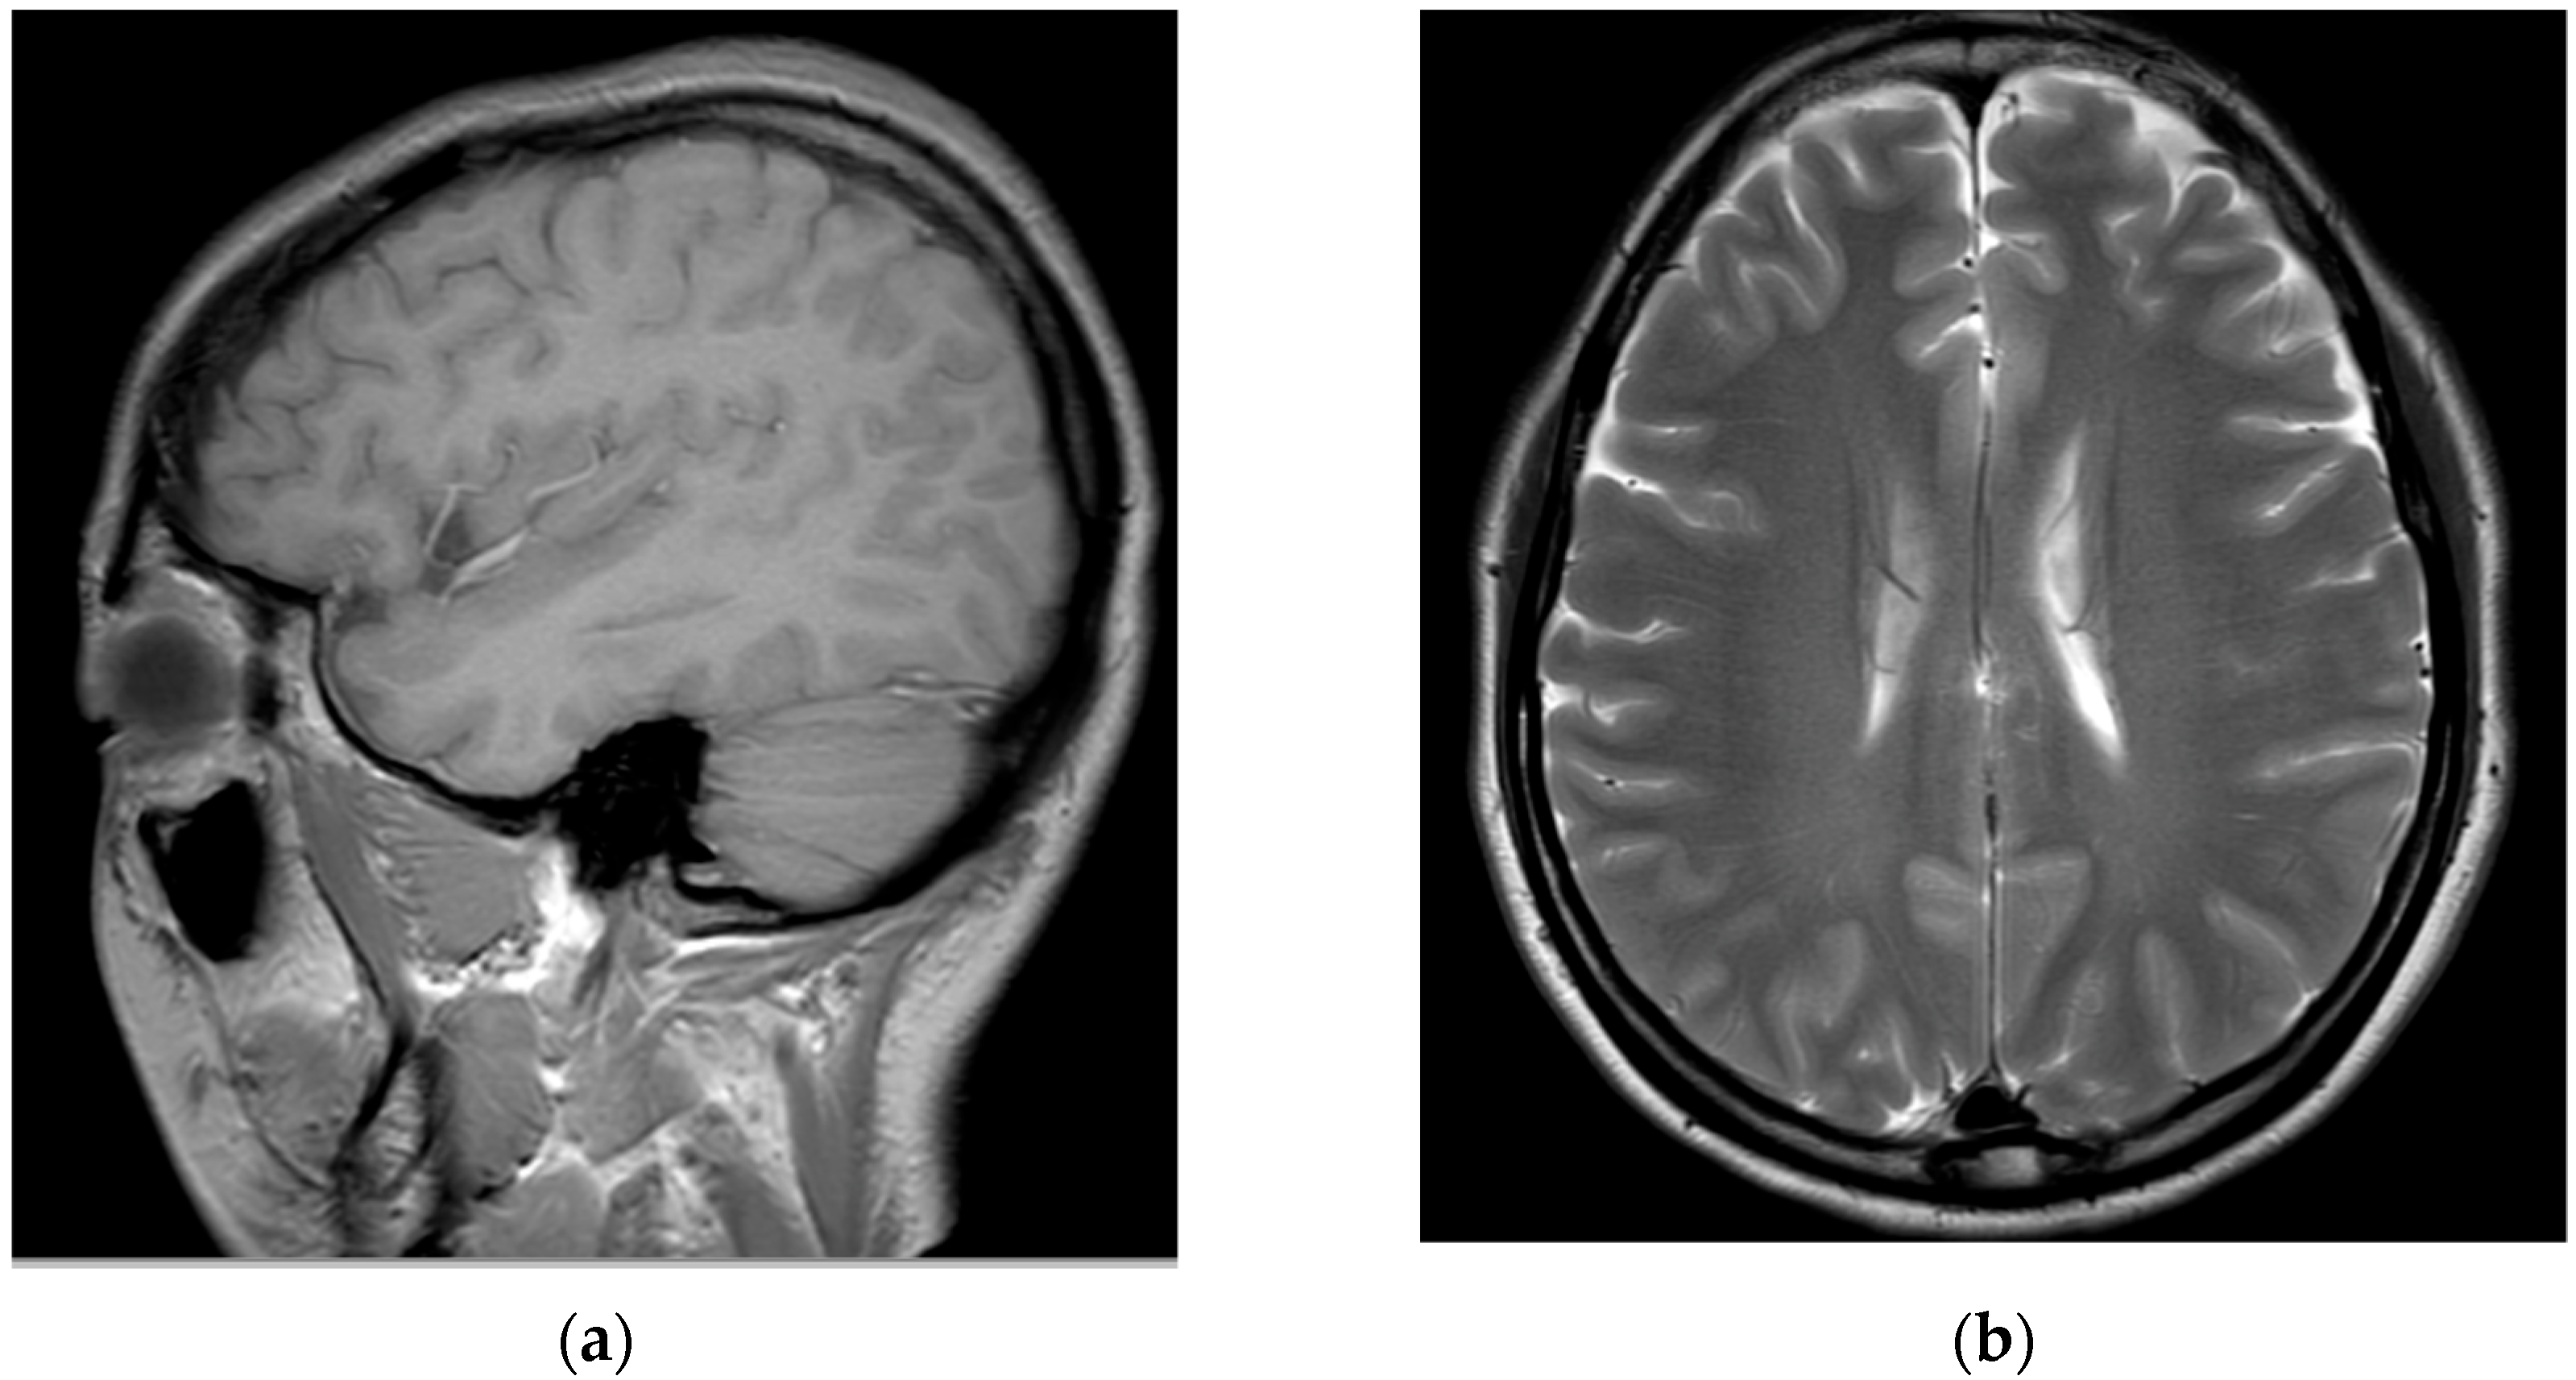

Subsequently, for left C6 impingement, the patient underwent CIESI under fluoroscopy using the C5/6 interlaminar approach. According to the medical records, when the Tuohy needle was inserted epidurally during the procedure, the patient experienced severe pain, described as burning and electric, in the left arm. Subsequently, a mixture of 3 mL of 1% lidocaine and 1 mL of dexamethasone was injected in the epidural space. Immediately after the procedure, the patient was in an alert mental state; however, severe dizziness, reduced blood pressure (BP 60/40), reduction of left arm motor function to motor grade 0, and loss of sensory function other than touch were observed. Blood pressure instability was relieved within approximately 1 h after the procedure with the administration of vasopressors, inotropes, and anticholinergics. However, motor weakness and sensory loss persisted in her left arm. Furthermore, 6 h after the procedure, the patient developed postdural puncture headache (PDPH) with a VAS score of approximately 7, after which she presented to the emergency department of our hospital. At the time of her visit, her vital signs were normal. On the second day of CIESI, the PDPH-related VAS score was 7. Upon physical examination, the manually tested muscle power of the left upper extremity was 2/5 proximally and 3/5 distally. Pressure and temperature discrimination, light touch, and vibration sensations decreased in the left upper arm. The remaining extremities and facial areas had intact motor and sensory functions. The patient complained of severe PDPH; therefore, the presence of gait disturbances could not be confirmed. Contrast-enhanced brain and cervical spine MRIs were performed on the second day of the procedure. After brain MRI, the assessment by the radiologist was of a “probable small amount of parafalcine subdural hematoma (SDH), left” (Figure 2).

Figure 2.

Brain magnetic resonance images obtained on the second day of the procedure: (a) T2-weighted sagittal image and (b) T2-weighted axial image. The assessment by the radiologist was of a “probable small amount of parafalcine subdural hematoma, left.” However, clear findings indicating a subdural hematoma are absent.